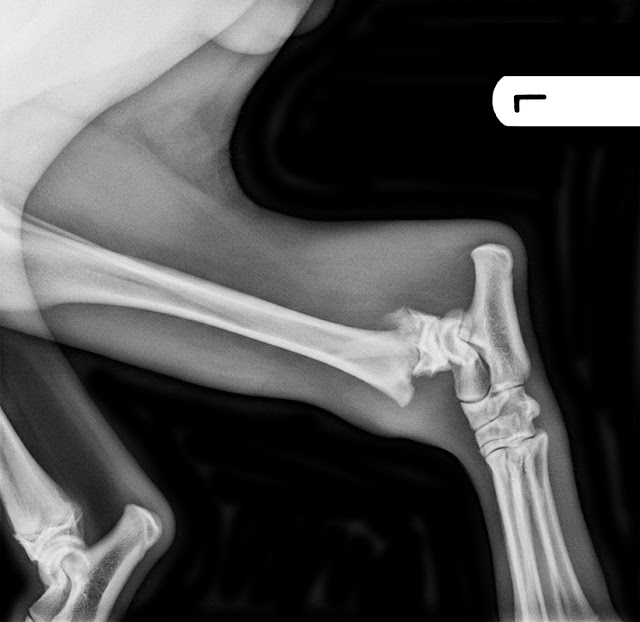

Fractura fisis distal

tibia, Salter Harris tipo II

En este caso, nuestro

paciente es un cachorro de Pastor Belga Malinois, de 5 meses, con 25 kg de peso

y extremadamente activo (típico de la raza) que se precipitó desde una ventana,

y viene con una cojera de no apoyo de su extremidad posterior izquierda.

Comenzamos con el estudio radiográfico y se obtienen las siguientes imágenes:

Como ya se ha comentado, se

trata de una fractura de la fisis distal de la tibia izquierda, Salter Harris

tipo II. En este tipo de fracturas el espacio para colocar implantes es mínimo

a nivel distal, por lo tanto no es fácil poner una placa de osteosíntesis y

todos los autores coinciden en que la resolución más adecuada es mediante

agujas de Kirschner.